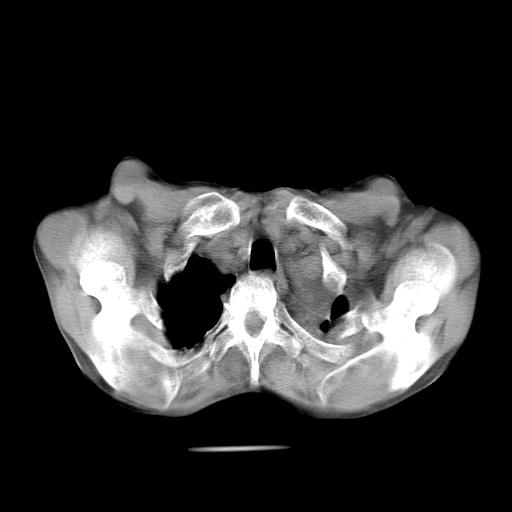

男  70岁,发烧咳嗽4天。盗汗,消瘦。无痰中带血丝,以前有肺tb病史,ct见,双肺tb,左侧胸廓塌陷,左胸膜肥厚粘连。纵隔移位,右侧胸腔积液,大家说说那个心影前左肺舌叶除了肺大炮还有炎症还是干酪性肺炎?有占位吗?我看纵隔淋巴结也大。

1)两肺继发性肺结核并左肺上叶肺不张,支气管扩张。2)双侧胸膜炎(胸膜增厚+少量胸腔积液)。

双肺继发性肺结核伴部分左肺毁损!

两肺继发性肺结核并感染,左肺上叶肺不张。建议ct增强。